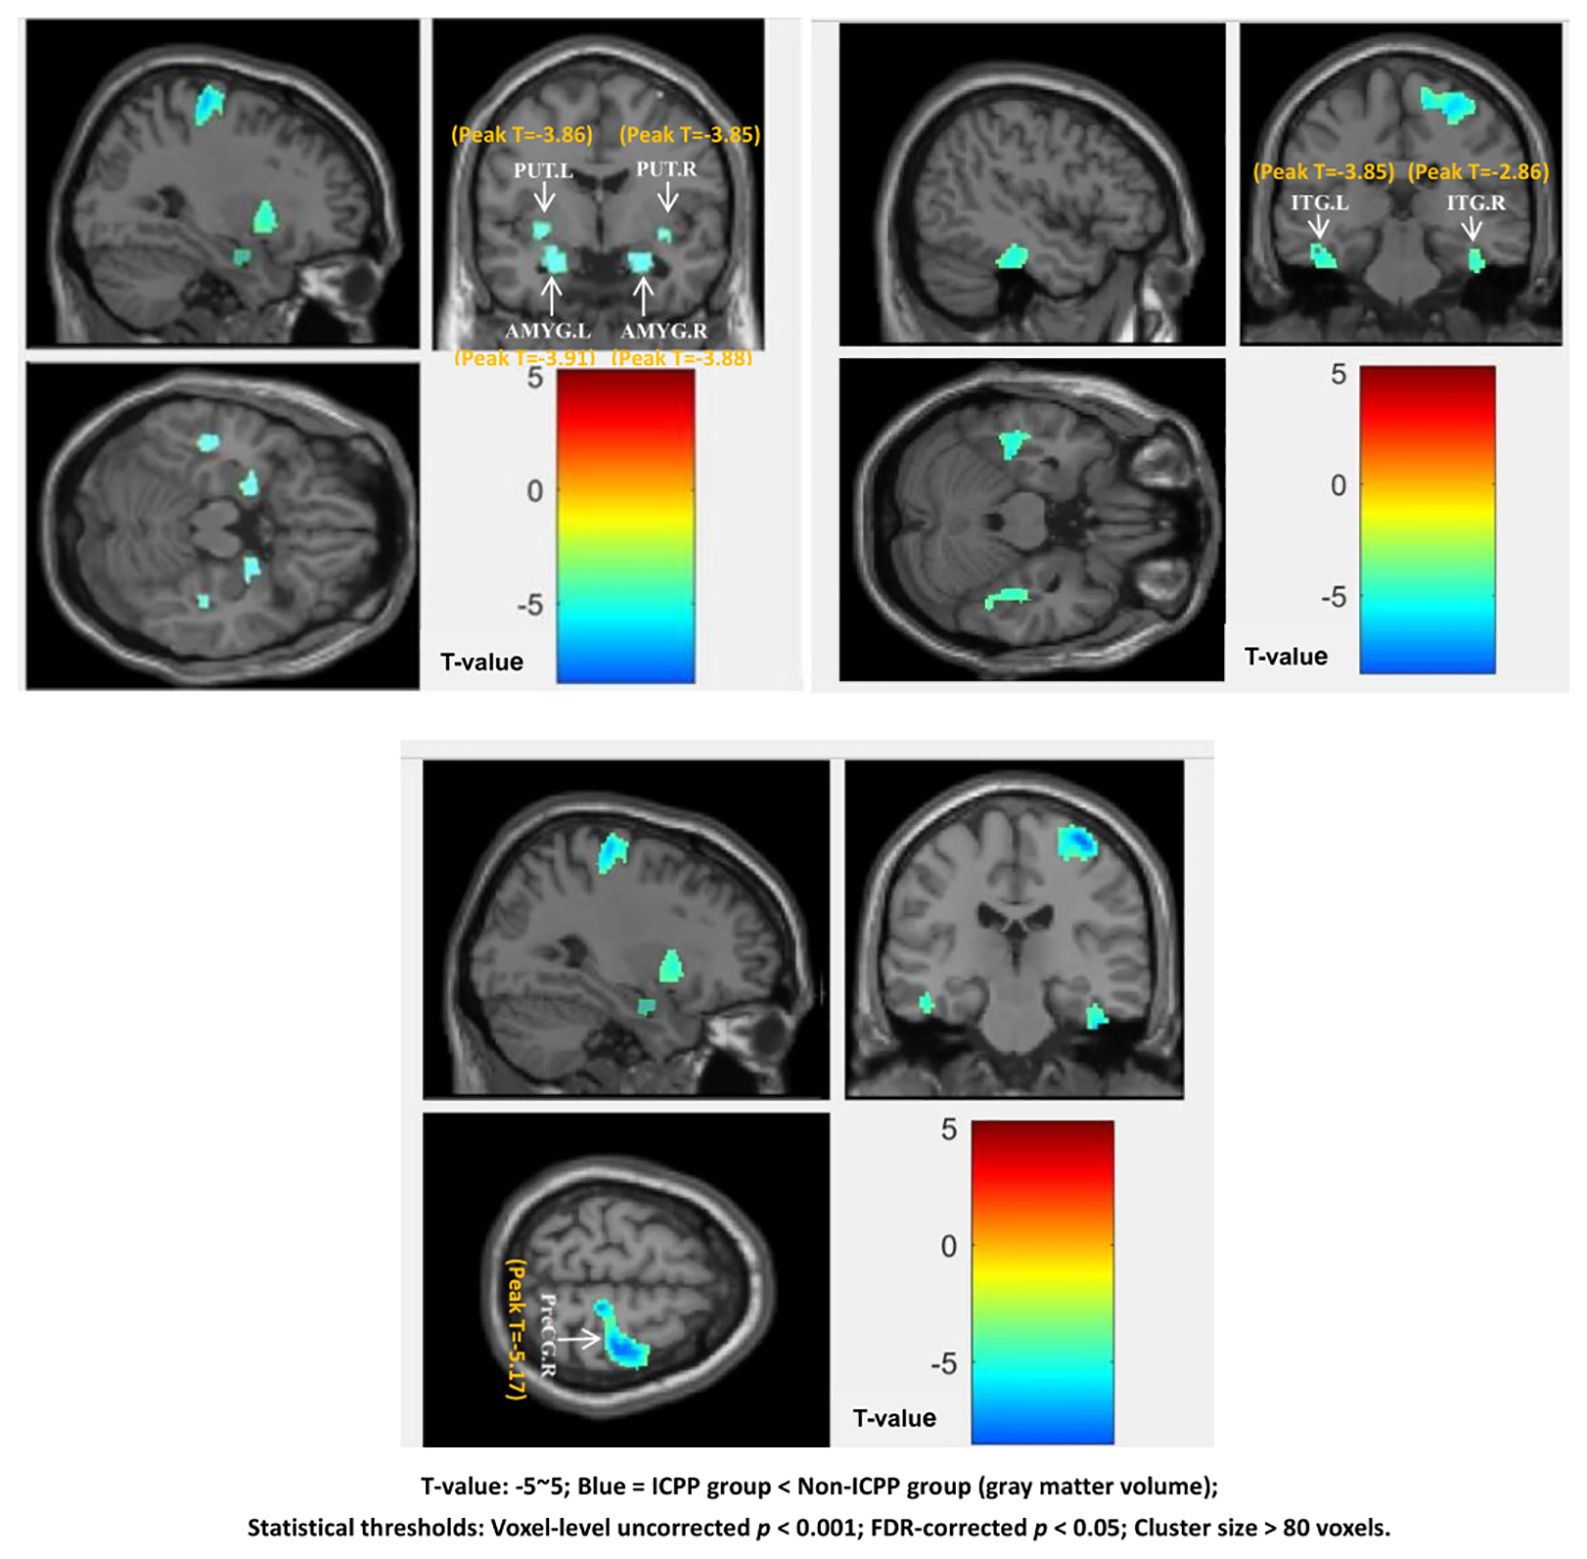

VBM analysis revealed that, compared to the non-ICPP group, the ICPP group exhibited reduced gray matter volume in multiple brain regions, including the right precentral gyrus, bilateral amygdala, bilateral inferior temporal gyrus, and bilateral putamen (p < 0.05, false discovery rate [FDR] corrected) (see Figure 3, Table 3). Cluster 5 (ITG.R, T=-2.86) is significant as it meets VBM’s criteria: uncorrected p < 0.001, FDR-corrected p < 0.05, and cluster size=122 voxels (>80 voxels).

Figure 3. Brain regions showing significant differences in grey matter volume between the ICPP and non-ICPP group. PreCG.R, right precental gyrus; AMYG.L, left amygdala; AMYG.R, right amygdala; ITG.L, left inferior temporal gyrus; ITG.R, right inferior temporal gyrus; PUT.L, left putamen; PUT.R, right putamen.The color bar on the right side of the figure indicates the range of T-values from -5 to 5, where negative T-values represent reduced grey matter volume in the ICPP group compared to the non-ICPP group (the darker the blue, the more significant the reduction). The peak T-value of significant clusters ranges from -5.17 (right precentral gyrus, cluster 1) to -2.86 (right inferior temporal gyrus, cluster 5). Statistical thresholds: voxel-level uncorrected p<0.001, FDR-corrected p<0.05, cluster size>80 voxels.”.

SBM results showed that, compared to the non-ICPP group, the ICPP group showed significantly thinner cortex in the right precentral gyrus (FDR-corrected, p < 0.05) (see Figure 4). Red regions (T≈4) in Figure 3 are trend-level (FDR-corrected p > 0.05 or small cluster size) and not significant; only the right precentral gyrus meets all criteria.